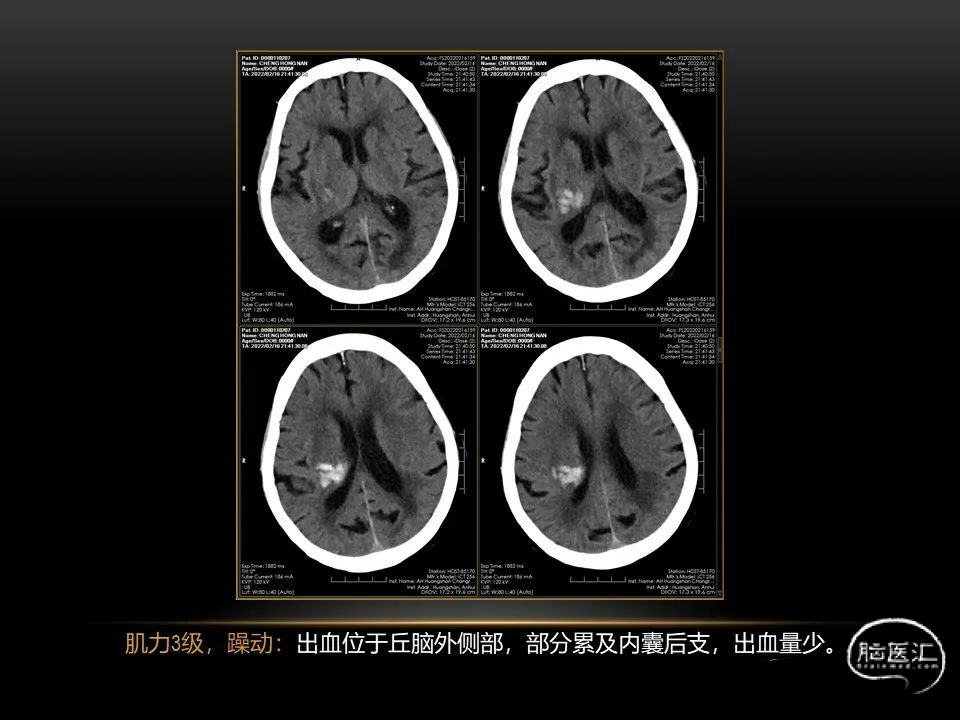

自发性脑出血临床上很常见,不同原因有特征性的出血部位。例如:基底节出血和丘脑出血大多是高血压性脑出血;脑叶出血,特别是多次复发的脑叶出血多见于老年人的脑血管淀粉样变。

自发性脑出血不仅仅累及内囊后肢才会出现偏瘫及偏身感觉障碍,病变累及大脑脚或辐射冠同样有可能有类似症状和体征。内囊、辐射冠、大脑脚等结构之间是延续的,只是不同区域不同名称而已。定位诊断需要对解剖结构概念清晰,读片准确辨认,灵活掌握。